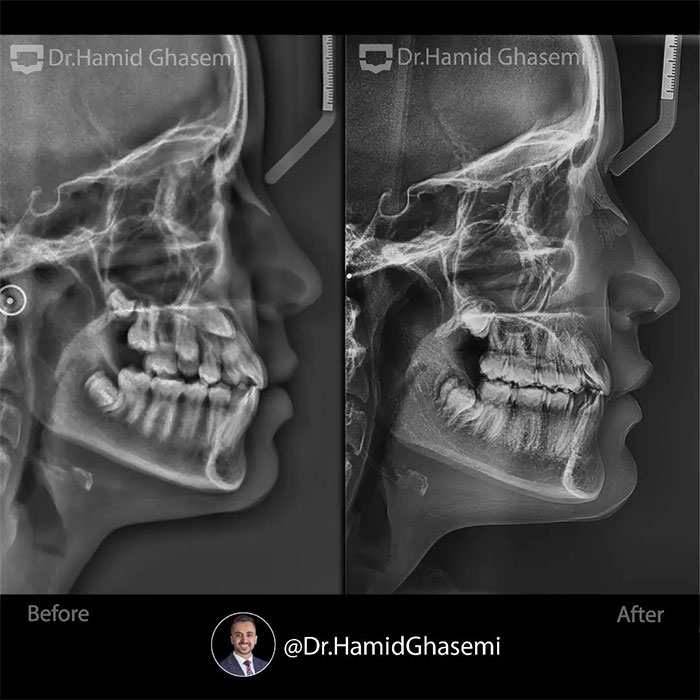

یک کیس خیلی جالب با مشکل جلوزدگی متوسط فک بالا و پایین (Bimaxillary dentoalveolar protrusion ) همراه با نهفتگی دوطرفه دندانهای نیش فک بالا. درمان با کشیدن دندان های نیش نهفته فک بالا و دندانهای پرمولر اول پایین انجام شد. تغییرات مثبت و قابل توجه در پروفایل و حالت لبهای بیمار پس از درمان و کسب اکلوژن کلاس ۱ ایده آل همچنان که دندانهای پرمولر اول بالا جایگزین دندانهای نیش نهفته در فک بالا شدند کاملا مشهود است.

This was such an amazing case with moderate bimaxillary dentoalveolar protrusion plus impacted bilateral upper canines. The case was treated by extraction of upper impacted canines and lower 1st premolars. Significant profile change achieved while upper 1st premolars substituted for upper canines properly with a solid perfect class 1 dental occlusion.